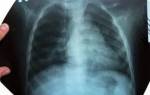

Для уточнения диагноза проводится рентгенография грудной клетки, оцениваются общий и биохимический анализы крови.

- Рентгенологическая картина: в начале болезни — инфильтрат с нечеткими границами. В случае прогрессирования воспаления — увеличение инфильтрата.